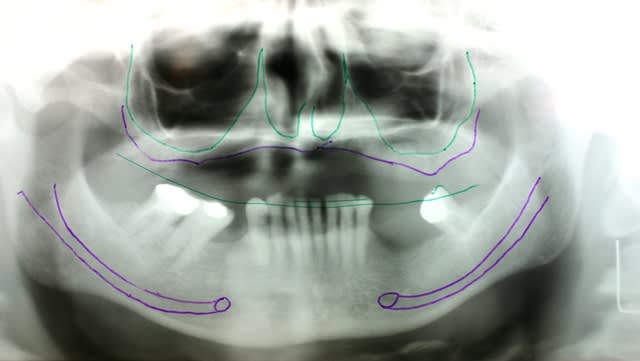

Résorption extrême chez patiente de 63 ans qui ne veut aucune greffe crânienne, aucun comblement sinusien et qui a à tout casser 2 mm sous les sinus et les fosses nasales ???

4 zygomatiques et 2 en secteur canin.

Des disks où tu peux , plus des plaques basales , et tu réhabilites de 6 à 6 .

PS Sauf que j ai posé 2 ptérygo et 2 zygo avec 2 canin ;-)

sauf que là pour une fois je dis trop de titane pour le trop peu d os qui reste

donc on ne pose que 7 implants mais qui ont une base d appui et une emprise qui emballe tout le maxillaire ( enfin ce qu il en reste...)

et là bien sûr aucune alternative à part la MCI car ces implants ne peuvent rester isolés